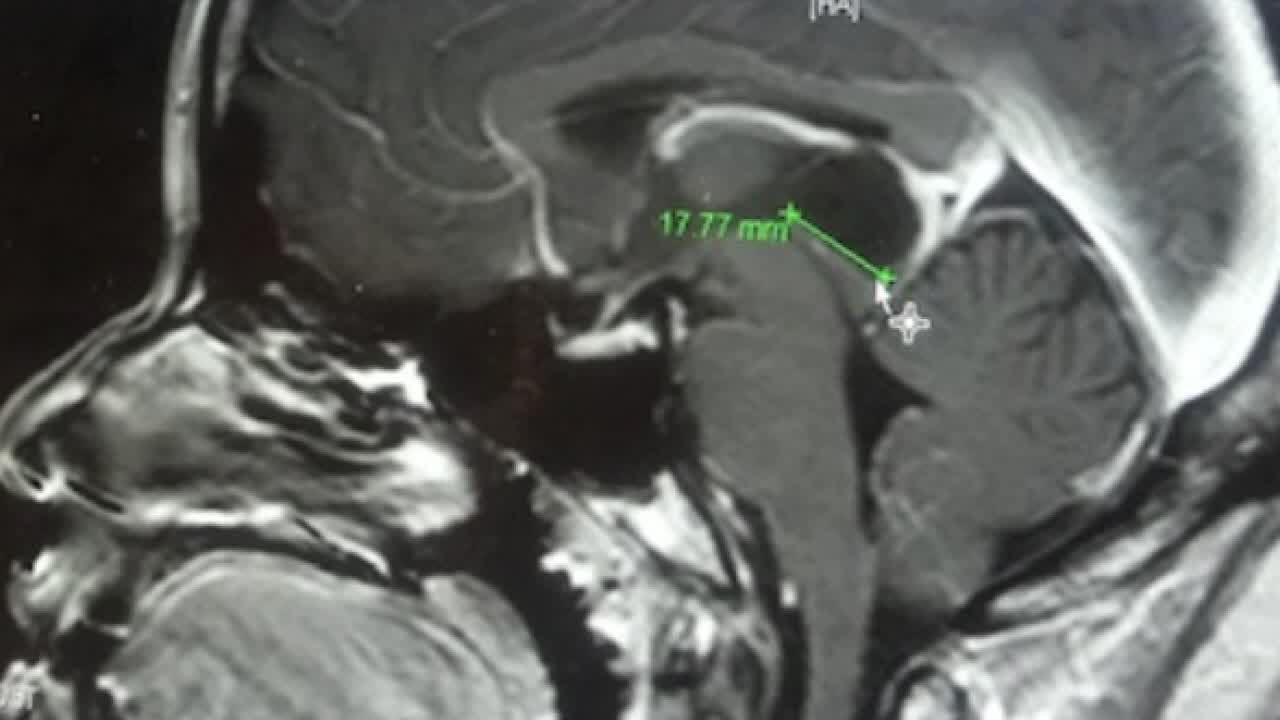

Prairie View nursing student with cyst on brain (rev)